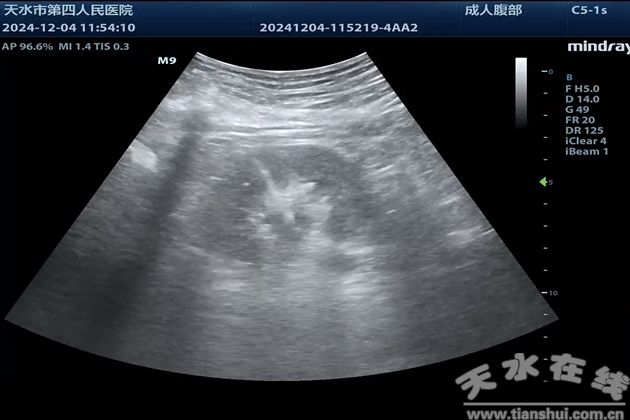

近日,天水市第四人民醫(yī)院功能檢查科超聲介入團隊?wèi){借精湛技術(shù),成功完成一例高難度超聲引導(dǎo)下經(jīng)皮腎穿刺造瘺術(shù)。

患者王某某,中年女性,因左側(cè)腰腹部間歇性絞痛突發(fā)加重緊急來院就診,急診彩超顯示:左腎重度積水,左側(cè)輸尿管上段擴張并內(nèi)結(jié)石。急診行輸尿管鏡下雙“J”管置入,因結(jié)核感染合并輸尿管多發(fā)息肉,置管未能成功。經(jīng)多學(xué)科會診討論,最終決定行超聲引導(dǎo)下經(jīng)皮腎穿刺造瘺術(shù)。

術(shù)前,功能檢查科超聲介入團隊對患者的病情進行了全面、細(xì)致的評估,排除禁忌癥后,予以該患者實施超聲引導(dǎo)下經(jīng)皮腎穿刺造瘺術(shù)。術(shù)中,超聲介入團隊?wèi){借嫻熟的操作與精準(zhǔn)的超聲定位,快速安全地完成了穿刺。術(shù)后,引流管通暢,大量膿性分泌物順利排出,位置固定良好。目前患者癥狀顯著緩解。此次手術(shù)的成功開展,彰顯了天水市第四人民醫(yī)院的專業(yè)實力,也為泌尿系統(tǒng)疑難病癥患者帶來了新的治療選擇。